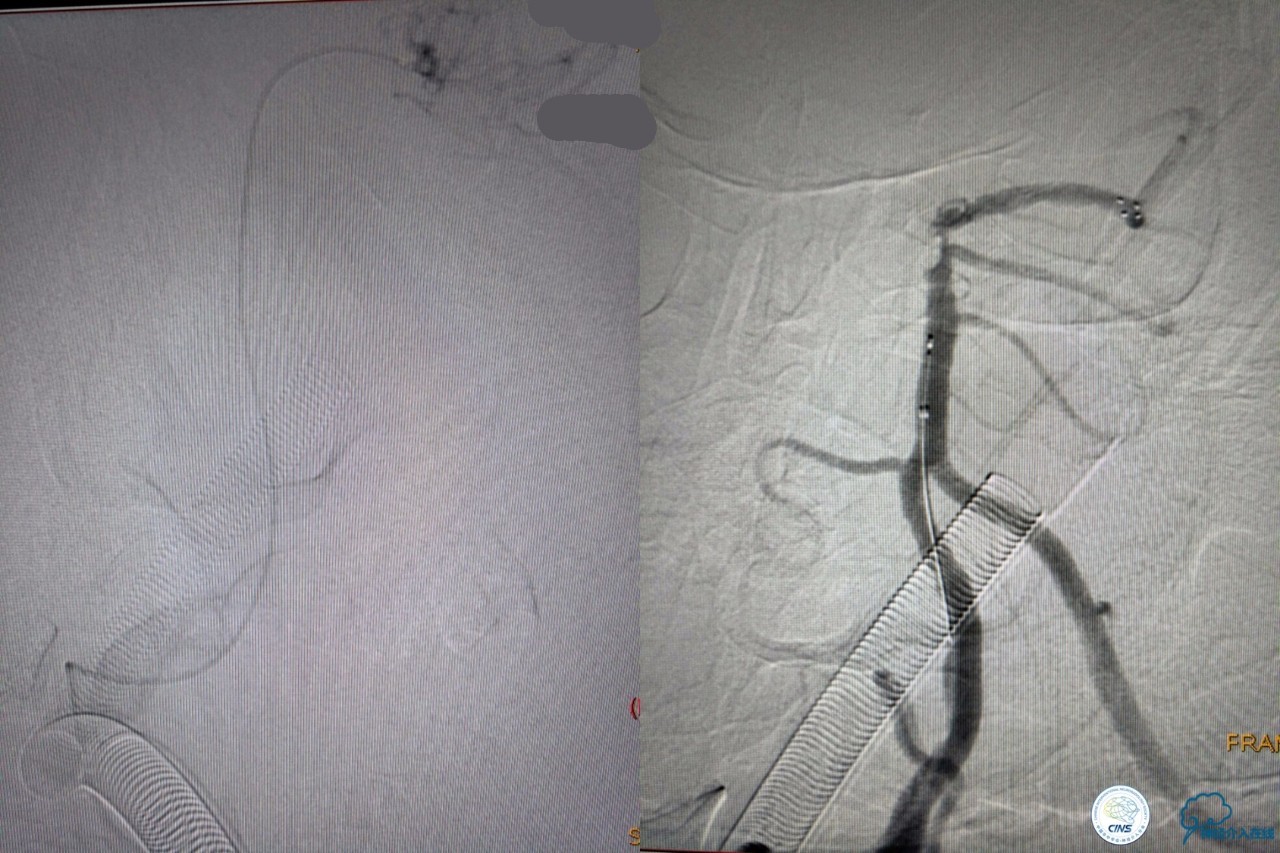

造影结果:右侧颈总动脉远端闭塞,前交通动脉开放,代偿方式:左侧颈内动脉→左侧大脑前动脉A1→前交通动脉→右侧大脑前动脉A1(反向)→右侧大脑中动脉供血区代偿。双侧大脑后动脉、右侧小脑上动脉及基底动脉顶端未见显影。

结合病史,体征及影像学,斟酌患者本次发病为基底动脉尖急性闭塞,发病机制:栓塞?右侧颈总动脉慢性闭塞?非责任血管,且代偿良好,暂时不需处理!

6F导引导管到位至RV2远端,rebar-18微导管及transand微导丝至右侧大脑后动脉P1远端。

solitaireAB4-20mm支架取栓。

基底动脉顶端仍有大量血栓,双侧大脑后动脉未见显影,双侧小脑上动脉再通。再次取栓?还是动脉溶栓?

决定导管内给予替罗非班6ml,复查造影BA顶端仍闭塞,第二次取栓。

第二次取栓后可见基底动脉顶端仍有大量血栓,右侧大脑后动脉开通,但左侧大脑后未见显影且左侧小脑上动脉闭塞!

第三次取栓,支架放入左侧大脑后取栓。

第三次取栓后,左侧大脑后动脉开通,但是栓子再次栓塞右侧大脑后动脉,血栓在基地动脉顶端来回左右摆动,下一次,怎办?血栓负荷太多,能够使用solumbar技术,能够没有颅内导管,没办法,换用更大的支架6-20mm,但费用增加不少,与家属沟通后同意使用,第四次取栓:

血栓负荷还是很大,左侧大脑后再通,但右侧大脑后又闭塞,只能第五次取栓,支架放到右侧大脑后动脉更远。

好大的血栓,支架释放后,血管无复流,拉一把!

没错,没看错!血管告捷实现再通,术中取栓的栓子如下。